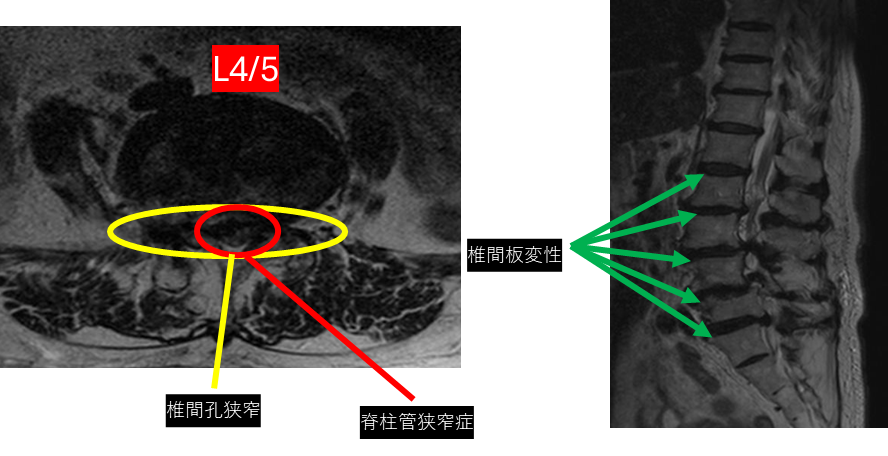

L1/2: 椎間板変性症

L2/3: 椎間板変性症

L3/4: 椎間板変性症、脊柱管狭窄症、左椎間孔狭窄

L4/5: 椎間板変性症、脊柱管狭窄症、両椎間孔狭窄

L5/S: 椎間板変性症、左椎間孔狭窄

以上の事が画像上認められます。

2/3、3/4、4/5、5/Sに椎間板変性症、脊柱管狭窄症、椎間孔狭窄 を認め、主症状の原因の可能性が高い。